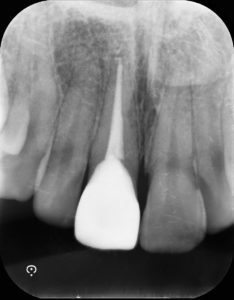

抜髄されてあった歯は打撲による外傷で歯が折れた過去があり、舌側に欠けて大きく歯が欠損していました。そこで、テンポラリークラウンにて歯肉のマネジメントを行い、シリコン印象材により丁寧に印象採得することで適合の良いクラウンを作ることができました。

根管治療により、術中、術後に痛みや違和感が出現する場合がある。

通常の根管治療において奏功しない場合、外科的処置や抜歯が必要になる可能性がある。

経年的に歯根破折が起き、抜歯が必要となる可能性がある。

失活歯は歯根破折が起き抜歯が必要となる可能性がある。